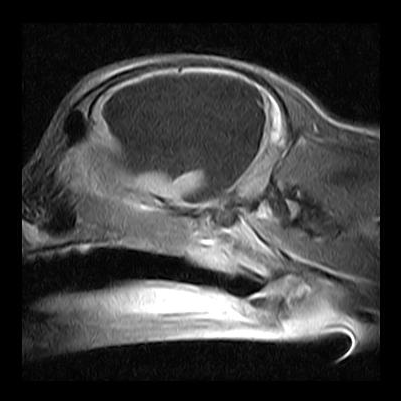

Neben kurzfristigen medikamentellen Therapien zur Reduktion des Gehirnwassers (Liquor) kann nur die Legung eines Abflussschlauches (Shunt) helfen. Hier wurde ein Ventil-Shuntsystem der Firma Christoph Miethke GmbH & Co. KG, Potsdam verwendet und leitet Druckflüssigkeit in den Bauchraum ab.

Man kann sehr gut den Umleiter am Schädel sehen und den Shuntschlauch bis in den Bauchraum verfolgen